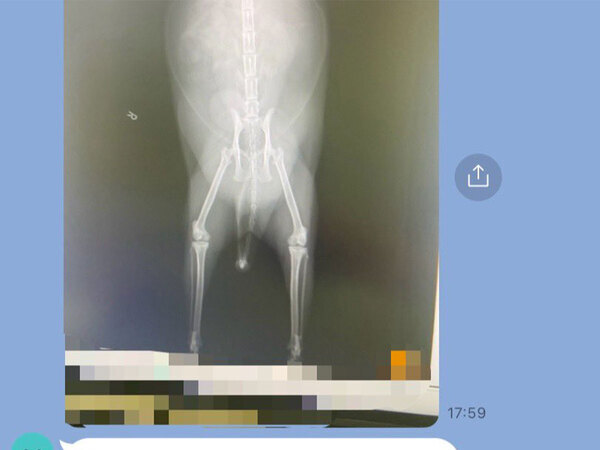

その後、妻からメッセージアプリ『LINE』で、診断の結果が送られてきたのですが…。

「お腹は脂肪」

お腹の膨らみは、腫瘍や骨折による腫れなどではなく、ただの脂肪だったのです…!